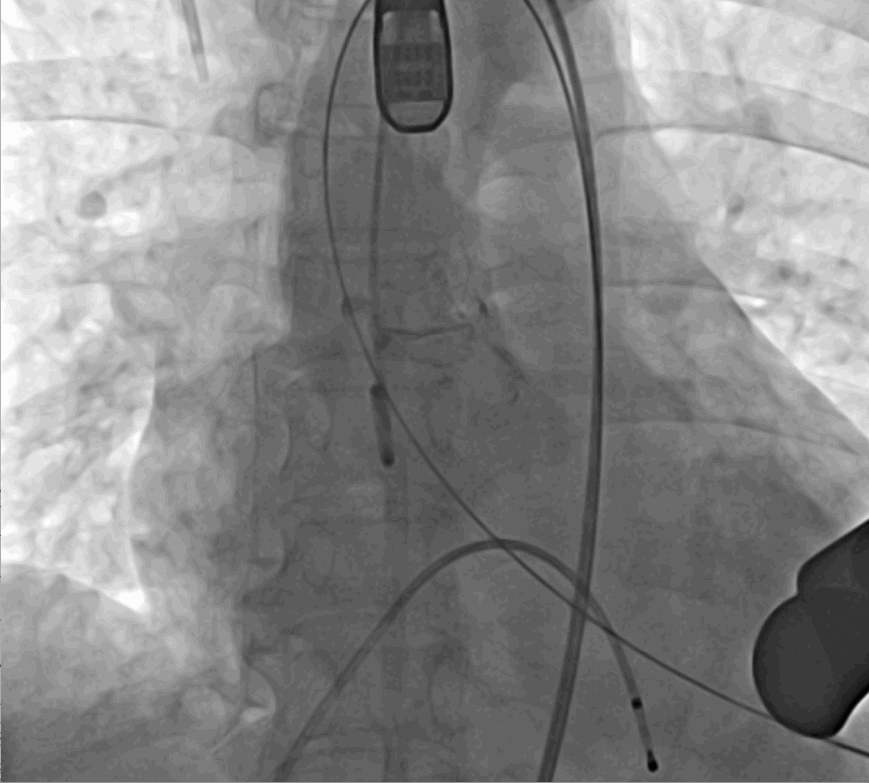

術(shù)中釋放定位鍵后DSA影像圖